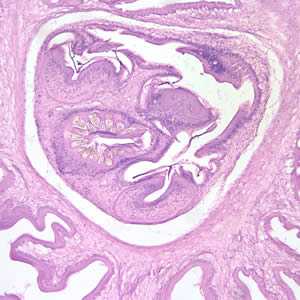

Larval Taenia solium.

Figure A: Larval Taenia solium cyst in a section of a lesion found in the right frontal lobe of a patient stained with hematoxylin and eosin (H&E), magnification 40×.

Figure C: Higher magnification (100×) of the cyst in Figures A and B. The parenchymatous portion of the cysticercus can be better observed.

Figure E: Cross-sections of cysticerci stained with H&E, at 40x magnification